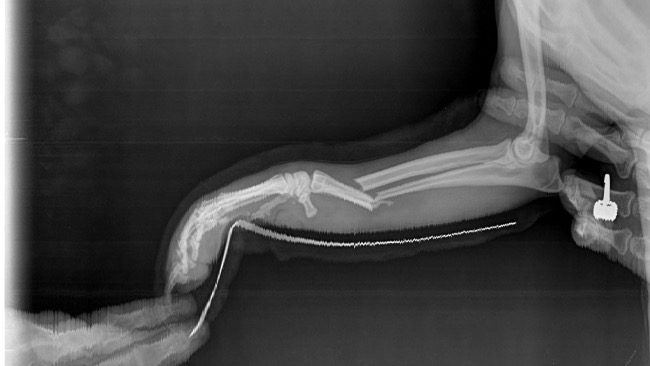

Na chwile obecna ma wstawione w łapkę dwa gwoździe by ustabilizować kości by mogły się zrosnąć .

Jeśli wszystko będzie się ładnie zarastać za około 3 miesiące odbędzie się kolejny zabieg usunięcia tych gwoździ .Tak to wyglada na chwile obecna . Jeszcze raz dziękuje za wszelka pomoc .